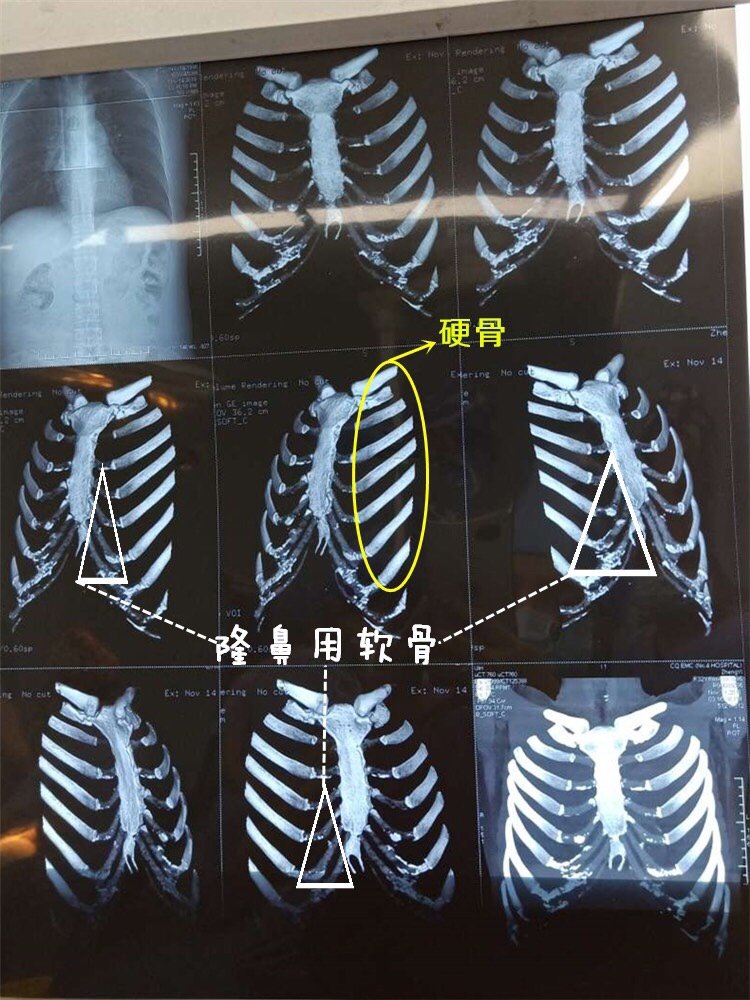

肋软骨钙化ct图片 第1页 图说健康

都说钙化的肋软骨不能做隆鼻 那什么是 新氧美容整形

肋软骨钙化 是怎么回事 怎么知道肋软 新氧美容整形

肋骨ct隆鼻图片 第1页 要无忧健康图库

肋软骨钙化是什么 肋软骨钙化了是不是 新氧美容整形